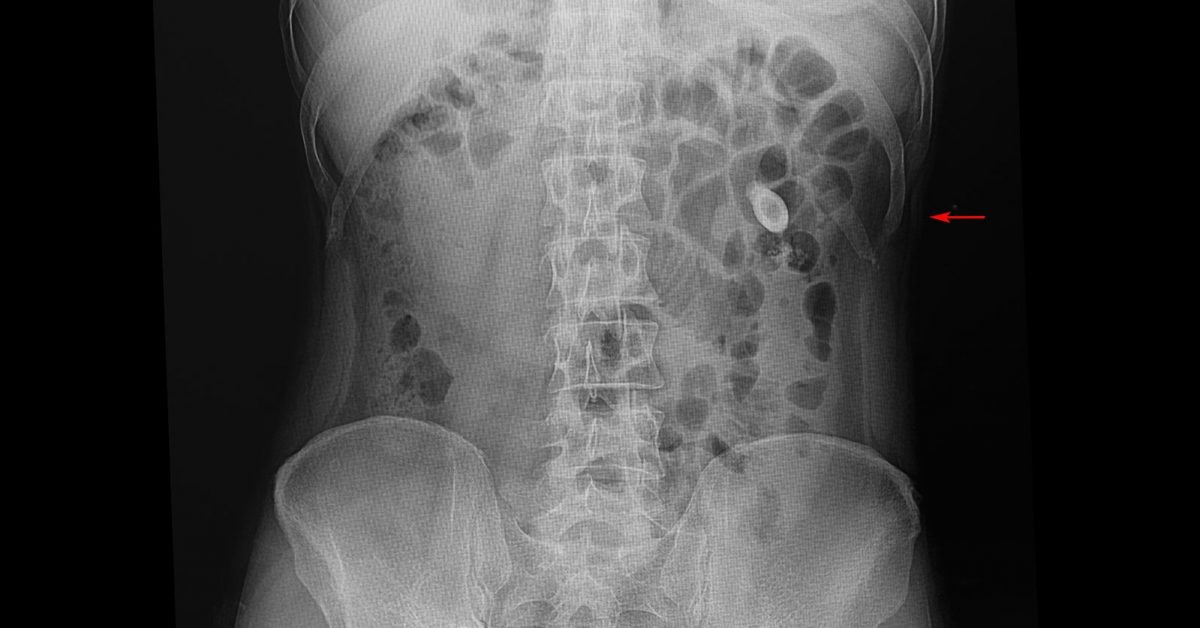

Can Kidney Stones Make Me Dizzy . kidney stones are usually found in the kidneys or in the ureter, the tube that connects the kidneys to your bladder. — passing a stone. Symptoms of kidney stones may include pain or pressure in the lower back, more. They may even go undetected and pass out painlessly when. very small kidney stones are unlikely to cause many symptoms. — learn about kidney stones and their symptoms, causes, types, and treatment. — kidney stones, also known as renal calculi, are hardened deposits of minerals that form in the kidneys and can. To stop your situation from getting. — kidney stones can be frustrating at best and agonizingly painful at worst. — kidney stones (also called renal calculi, nephrolithiasis or urolithiasis) are hard deposits made of minerals and salts.